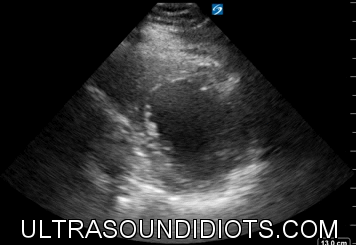

D-sign

This "letter" sign can be seen in both volume and pressure overload of the RV

To differentiate pressure overload (like a PE) from simple volume overload, the D-Sign must be present during this phase of the cardiac cycle

Systole (and Diastole) vs. Diastole alone for volume overload